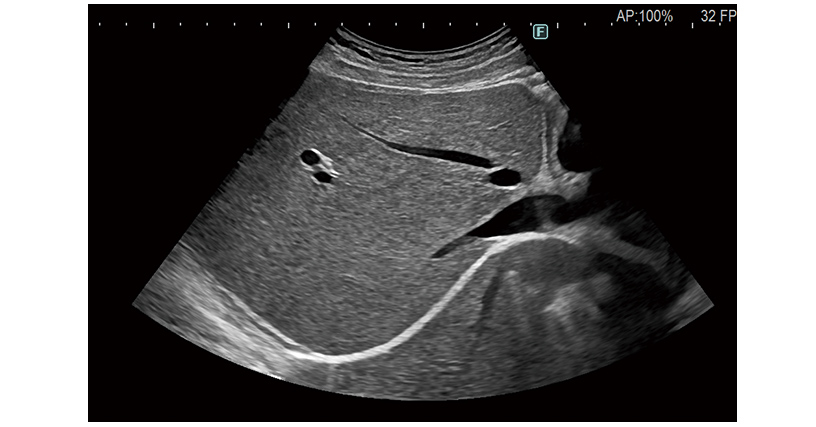

Flexibly responding to users' individual needs across the range of clinical disciplines, the ARIETTA 850 DeepInsight brings diagnostic imaging without compromise.

Further refinement of technologies harnessing high quality “sound” gives rise to our highest premium class performance yet.